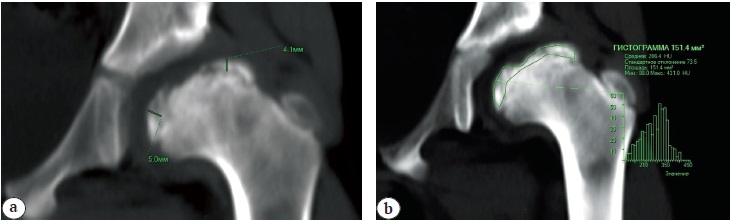

The results of MSCT of the hip joints showed that in all patients, during the initial studies, there was a total lesion of the femoral head with partial preservation of the marginal surfaces of the epiphysis. The subchondral necrosis zone was measured when assessing the height of the lateral, central and medial parts of the head. A total decrease in the height of the central part was observed in 30% of patients, subtotal — in 70%. Densitometric characteristics of the density of the fragmented femoral head according to the histogram showed increased mineralization by an average of 81.8 ±15.9 units. Houndsfield (HU) compared with a healthy femoral head (Fig. 2).

Fig. 2. Computed tomography of the hip in a patient with Perthes disease (Catterall IV) and hip subluxation: a — method of measuring the zone of subchondral necrosis; b — assessment of femoral head density using the histogram technique of the allocated volume of the studied zone